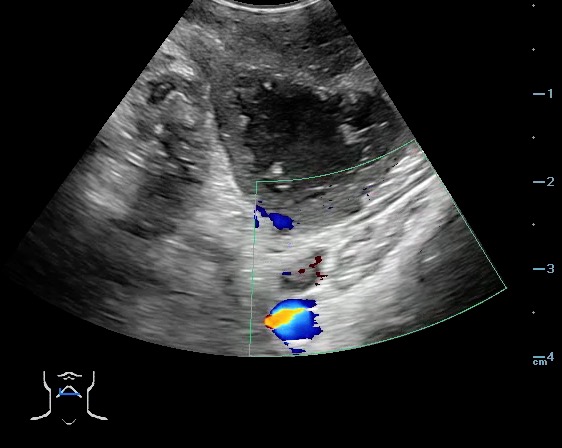

- Peritonsillar abscess is visualized as a hypoechoic or complex cystic structure

- Ultrasound-guided needle aspiration of a PTA:

- Figure 45. and 46. PTA aspiration

- The carotid artery is seen as an anechoic tubular structure along the posterolateral aspect of the tonsil on ultrasound. Its relationship to the abscess cavity should be determined. Color Doppler can help locate the carotid artery.

- Figure 47 and 48. PTA with color Doppler of carotid artery